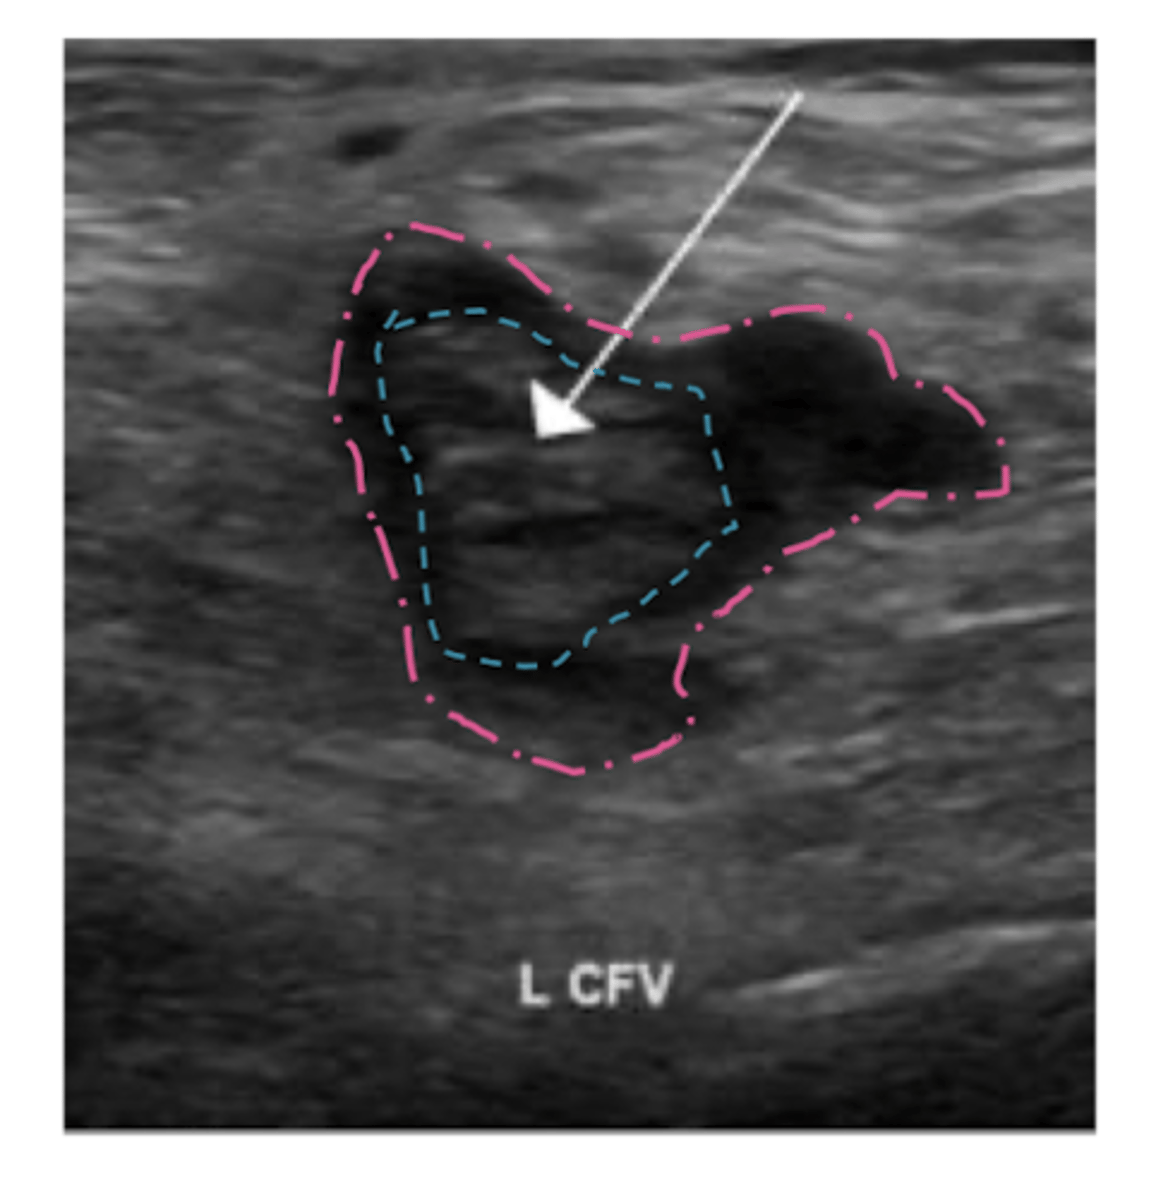

What is initial study of choice for DVT? second line?

duplex u/s of inguinal region, thigh, and popliteal area

second line: contrast venogram

<p>duplex u/s of inguinal region, thigh, and popliteal area</p><p>second line: contrast venogram</p>